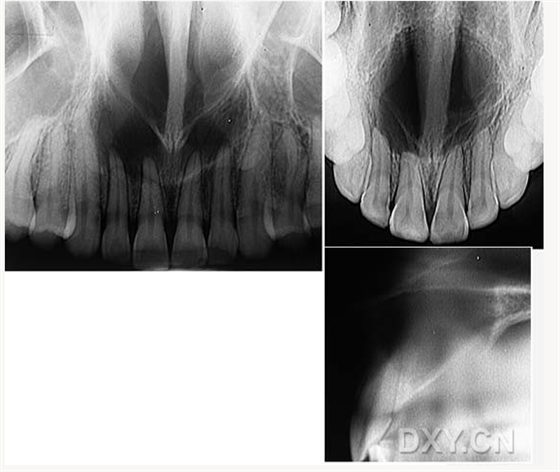

鼻鄂囊腫

根尖囊腫